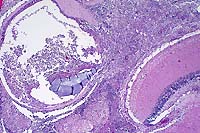

- Case 8-2. Otic vesicle, Brain. The otic vesicle is

heavily infiltrated by inflammatory cells and fibrin, and contains

a mineralized otolith. The connective tissue between the brain

and otic vesicle is similarly infitrated by abundant inflammatory

cells.

Brown

& Brehn, 40x obj

- Case 8-2 . Skull. Some macrophages in the exudate

surrounding the otic vesicle contain abundant Gram positive cocci.

20x

obj

- Case 8-2.Gill filaments and lamella. The interlamellar

space is partially filled between most gill lamella by an infiltrate

of macrophages, lymphocytes, and fewer mucus cells and/or epithelial